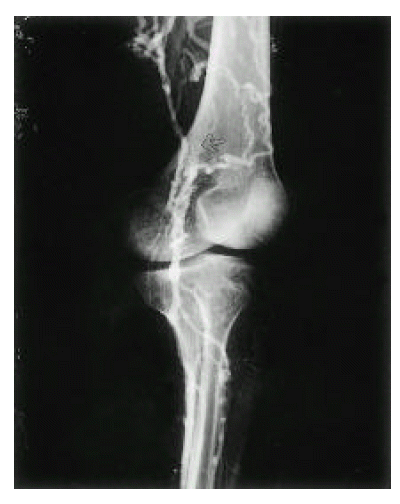

A 26-year-old woman was admitted for dyspnea, coughing and generalized edema for the last 5 months. She had a symptoms complex of recurrent oral aphtous ulcer, genital ulcer, erythema nodosum like skin lesions, uveitis and positive Pathergy test, and was diagnosed to have BD according to the diagnostic criteria proposed by the International Study Group for Behçet’s disease5). She gave no history of smoking, consumption of alcohol or any drugs. Two years ago, bypass surgery was performed due to deep vein thrombosis of left lower extremity (Fig. 1, 2). At that time, she did not follow-up and was not prescribed for any medication. On physical examination, the patient was uncomfortable and slightly pale. She became dyspneic on supine for the examination. No rash or lymphadenopathy was found. There was marked edema over the face, neck, both shoulders, anterior chest and lower extremities. Also, collateral vessels formation in the anterior chest wall and abdomen were noticed. Diminished breath sounds were present over both lung fields. The abdomen was distended and non-tender, but a fluid wave and shifting dullness were present. The liver was palpable 5 cm below the costal margin, but the spleen was not felt and no masses were palpable.

Fig. 2.

Venography of left lower extremity. Popliteal vein is abruptly obliterated (arrow) and superficial femoral vein is not opacified. Multiple collateral vessels are shown.